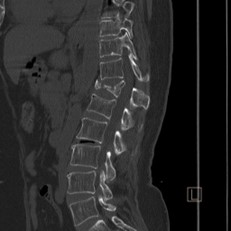

Case courtesy of Dr Hani Makky Al Salam, Radiopaedia.org, rID: 18568

Given the patient’s history of a fall along with spinal tenderness, you order an x-ray that shows an acute T12 compression fracture. Subsequent CT imaging shows an absence of ligamentous injury or cord involvement. Pain control is achieved using IM ketorolac, a lidocaine patch, and calcitonin nasal spray. Spine surgery is consulted and recommends non-operative management. The patient is instructed to follow up with her primary care physician and spine surgeon and endorses understanding.